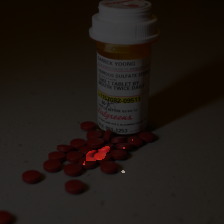

blocks.9.mlp.fc1-40

human annotations

- pill bottle

- pill bottles

- pill bottles

predicted caption

Rounded objects